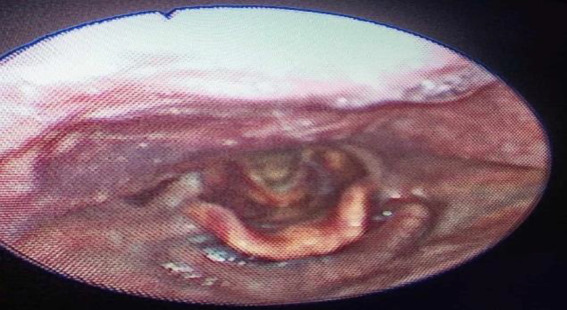

Case report: We present the case of a 74-year-old man who was on oral anticoagulation by acenocoumarol and presented with acute laryngeal dyspnea. The final diagnosis of pharyngo-laryngeal hematoma secondary to hypercoagulation was made based on the clinical, biological, and radiological features. Therefore, conservative management was initiated. Drug interactions between anticoagulants and macrolides were the probable underlying causes of excessive anticoagulation.